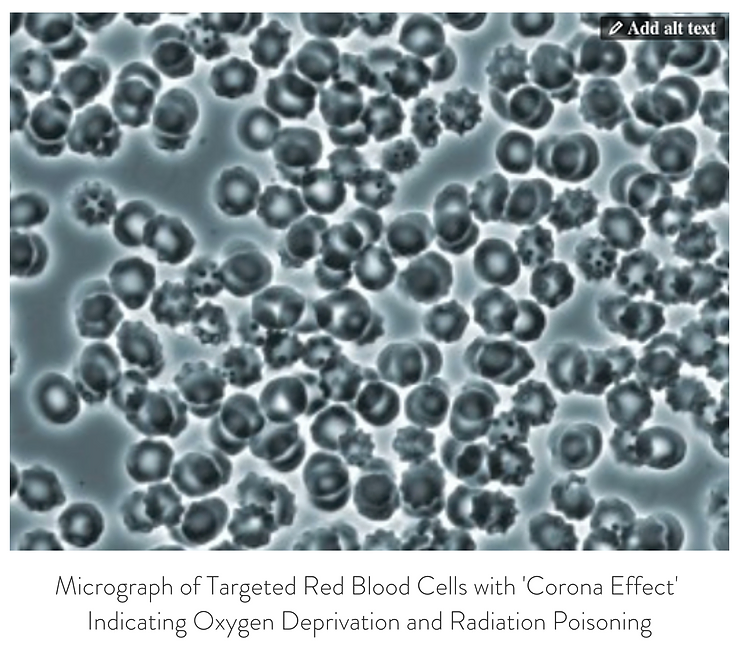

Decompensated acidosis of the body fluids causes erythrocytic or red blood cell membrane degeneration and genetic mutation causing the conditions of rouleau, membrane degeneration causing the spiking or knobing or ‘Corona Effect’, acanthocytosis, erythrocytic symplastism or red blood cell clotting, thrombosis and disseminated intravascular coagulation (DIC). There are at least eight major contributing toxic factors that cause the increased levels of acidity in the body fluids leading to a significant decline in the alkaline design of the major body fluids (See Illustration 2: Interstitial fluids of the Interstitium organ, the intravascular fluids and the Intracellular fluids) from their ideal pH of 7.365 to an unhealthy pH of 7.265 to 7.165.

Live and Dried Blood smears are both non-invasive blood tests that were used in viewing anatomically the conditions of the red and white blood cells in Disseminated Intravascular Coagulation (DIC), Thrombosis, Rouleau, the ‘Corona Effect’ and Acanthocytosis. (See Phase Contrast Micrograph 7)[12]